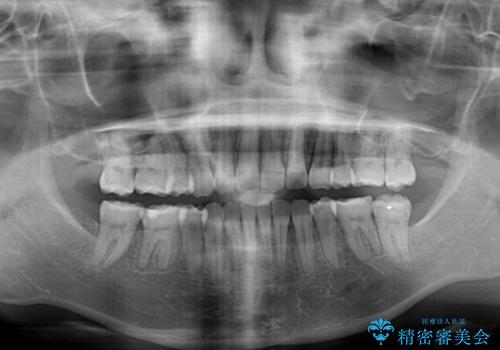

- 上の前歯の出っ歯とでこぼこの歯並びを気にして来院された患者様です。

口元を積極的に引っ込めるために、上下左右の小臼歯4本を抜歯することとしました。

4本の歯を抜歯したことで、飛び出していた口元が引っ込み、横顔が大きく改善されました。

咬み合わせが悪化することのないようにスペースを閉じていくことができ、比較的スムーズに治療を進めることができました。